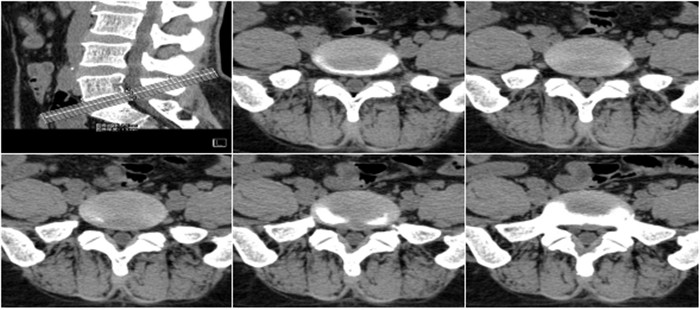

明峰CT搭載了領(lǐng)先的硬件技術(shù)平臺(tái)及系統(tǒng),強(qiáng)大的掃描能力可滿足臨床的各種要求,呈現(xiàn)更極致的細(xì)節(jié),為各臨床科室提供高品質(zhì)的圖像。薄層掃描,消除部分容積效應(yīng),提高各向同性。配合高分辨率算法,有助于細(xì)微結(jié)構(gòu)和形態(tài)學(xué)顯示。